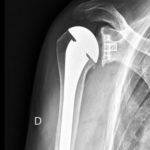

Le but de la prothèse de l’épaule est d’enlever les zones d’os et de cartilage qui sont usées, et de les remplacer par des pièces artificielles ayant les mêmes formes.